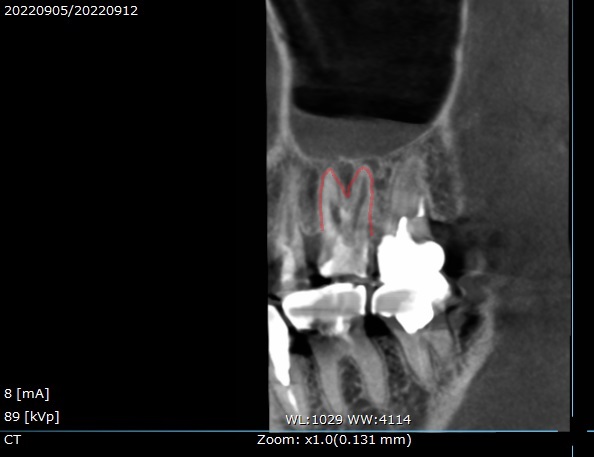

CTは色々な場所から見ることができます。

顔の正面からこの歯を見てみると、

このような状態。

先程と同じで、

根の先に膿が溜まっており(青)

上顎洞内部で、炎症が起こっています(赤)